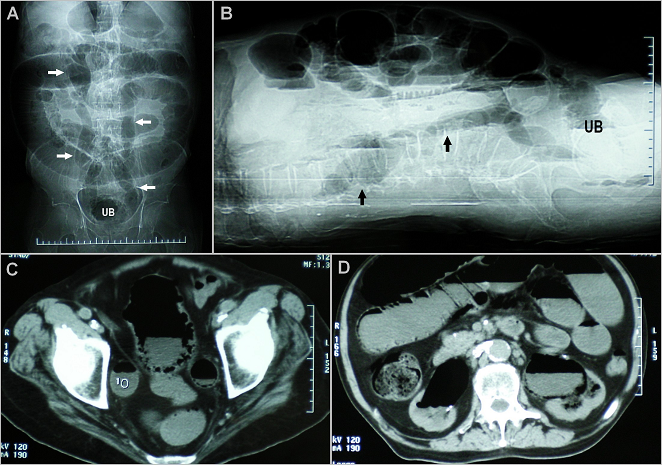

A 70-year-old man presented to the Emergency Department with lower abdominal pain, abdominal distention and fever of 3 days duration associated with increased urinary frequency, urgency and pneumaturia. He was known case of type 2 diabetes mellitus on oral anti-diabetic agents for the past 15 years. On Physical examination, he had a temperature of 38, 8°C and a diffuse abdominal tenderness without any peritonism signs. Laboratory investigations showed leukocytosis (27500/µl), C-reactive protein 74 mg/l and serum creatinine 210 mmol /l. Urinalysis revealed pyuria and culture grew Escherichia Coli. Abdominal radiography (A, B, arrows) and computed tomography (C and D) revealed presence of gas within the wall and the lumen of the urinary bladder (UB), the ureters and the collecting systems. The patient was diagnosed as having emphysematous cystitis with concomitant bilateral emphysematous ureteritis and pyelitis. Given that there were no gas pockets or fluid collections seen within the renal parenchyma or in the perinephric tissues, emphysematous pyelonephritis was ruled out. Gas appearance inside the urinary system can be also caused by fistulas related to the gastrointestinal system, urinary system's interventional procedures, trauma or urethrally introduced objects (homosexuals). Our patient was treated with intravenous antibiotic, indwelling urinary catheter and insulin. Within 7 days, he had complete clinical and radiographical resolution of the gas in his urinary system, and his renal function returned to baseline. Emphysematous cystitis is a severe infection of the bladder due to gas-producing bacteria, often occurring in the patients with poorly controlled diabetes. Delayed diagnosis may lead to extension to the upper urinary tract, which seems to have happened in our patient.